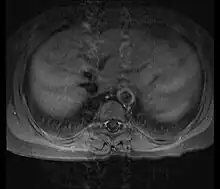

Axial T1-weighted post-gadolinium MRI in a patient with Takayasu arteritis showing thickened, enhancing aortic wall, consistent with large vessel vasculitis

Although the cause of Takayasu arteritis is unknown, the condition is characterized by segmental and patchy granulomatous inflammation of the aorta and its major derivative branches. This inflammation leads to arterial stenosis, thrombosis, and aneurysms.[4] There is irregular fibrosis of the blood vessels due to chronic vasculitis, leading to sometimes massive intimal fibrosis (fibrosis of the inner section of the blood vessels).[6] Prominent narrowing due to inflammation, granuloma, and fibrosis is often seen in arterial studies such as magnetic resonance angiography (MRA), computed tomography angiography (CTA), or arterial angiography (DSA).